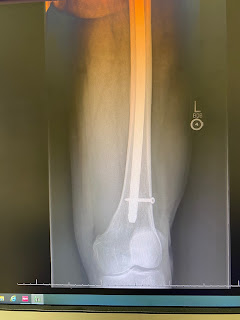

Good news was the doctors said that it was fine for me to try riding on a trainer. This is a big step in my recovery and I will set up my bike in the back yard with flat pedals on te trainer so that I can use it with street shoes. Hopefully this weekend I'll be pedaling again for the first time since July 5th. Wish me luck . If it does not hurt I'll be doing it daily as the leg permits. I know that getting blood flow to the area and some light loads on the bone will aid in healing.

Riding.....first I have to be able to walk again-doctors say if I listen to them I should heal up well. So far I have made leaps and bounds beyond what the nurses and PT people expected but hey-I'm 67 so I have to be realistic and figure that I'll take longer to heal this time around. What I am saying is that I'm not all fired up to ride ASAP- I'm all fired up to walk and to be able to get the hell out of my house again. Don't get me wrong, I love my house but I am more than ready to spend some quality away time from it. I miss my shop and I miss my mobility. I know that I could be way worse off and I'm thankful that my injury was a simple one........and I know that if I don't give it time to heal I will regret it for the rest of my life. So, yes- I will ride again but no hurry on that one.